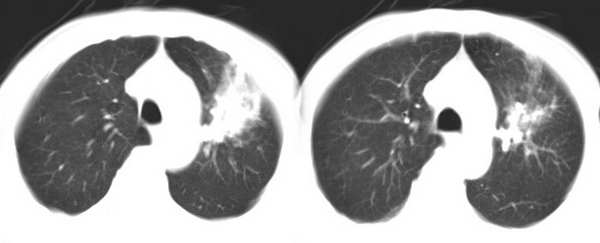

左肺上叶胸膜下不规则团块阴影,内见空泡,边缘光整,肺纵比率>50%,支持左肺癌的诊断。

其内透光影仔细观察像是支气管,病灶周围有渗出改变,该病灶不考虑感染性病变,机化性肺炎能排除吗

理由:1 病灶有恶性肿瘤的特征:空泡征,毛刺,棘状突起

左上肺病灶与胸膜脂肪线存在,未见明显胸膜凹陷征,虽然病灶边缘不规则,但未见明显“短毛剌、切迹征、免耳征、血管束集征”,其间亦见条索状、斑点状影,认为左上肺结核或炎性病变>周围型肺癌。

病灶比较虚 周围有明显渗出 卫星灶及条素影 病灶边缘有棘突 胸膜外脂肪层存在考虑结核

考虑肺结核可能性大。理由1.病灶形态不规则,其周有卫星灶,2.病灶没有毛刺征,灶周出现粗大索条影.